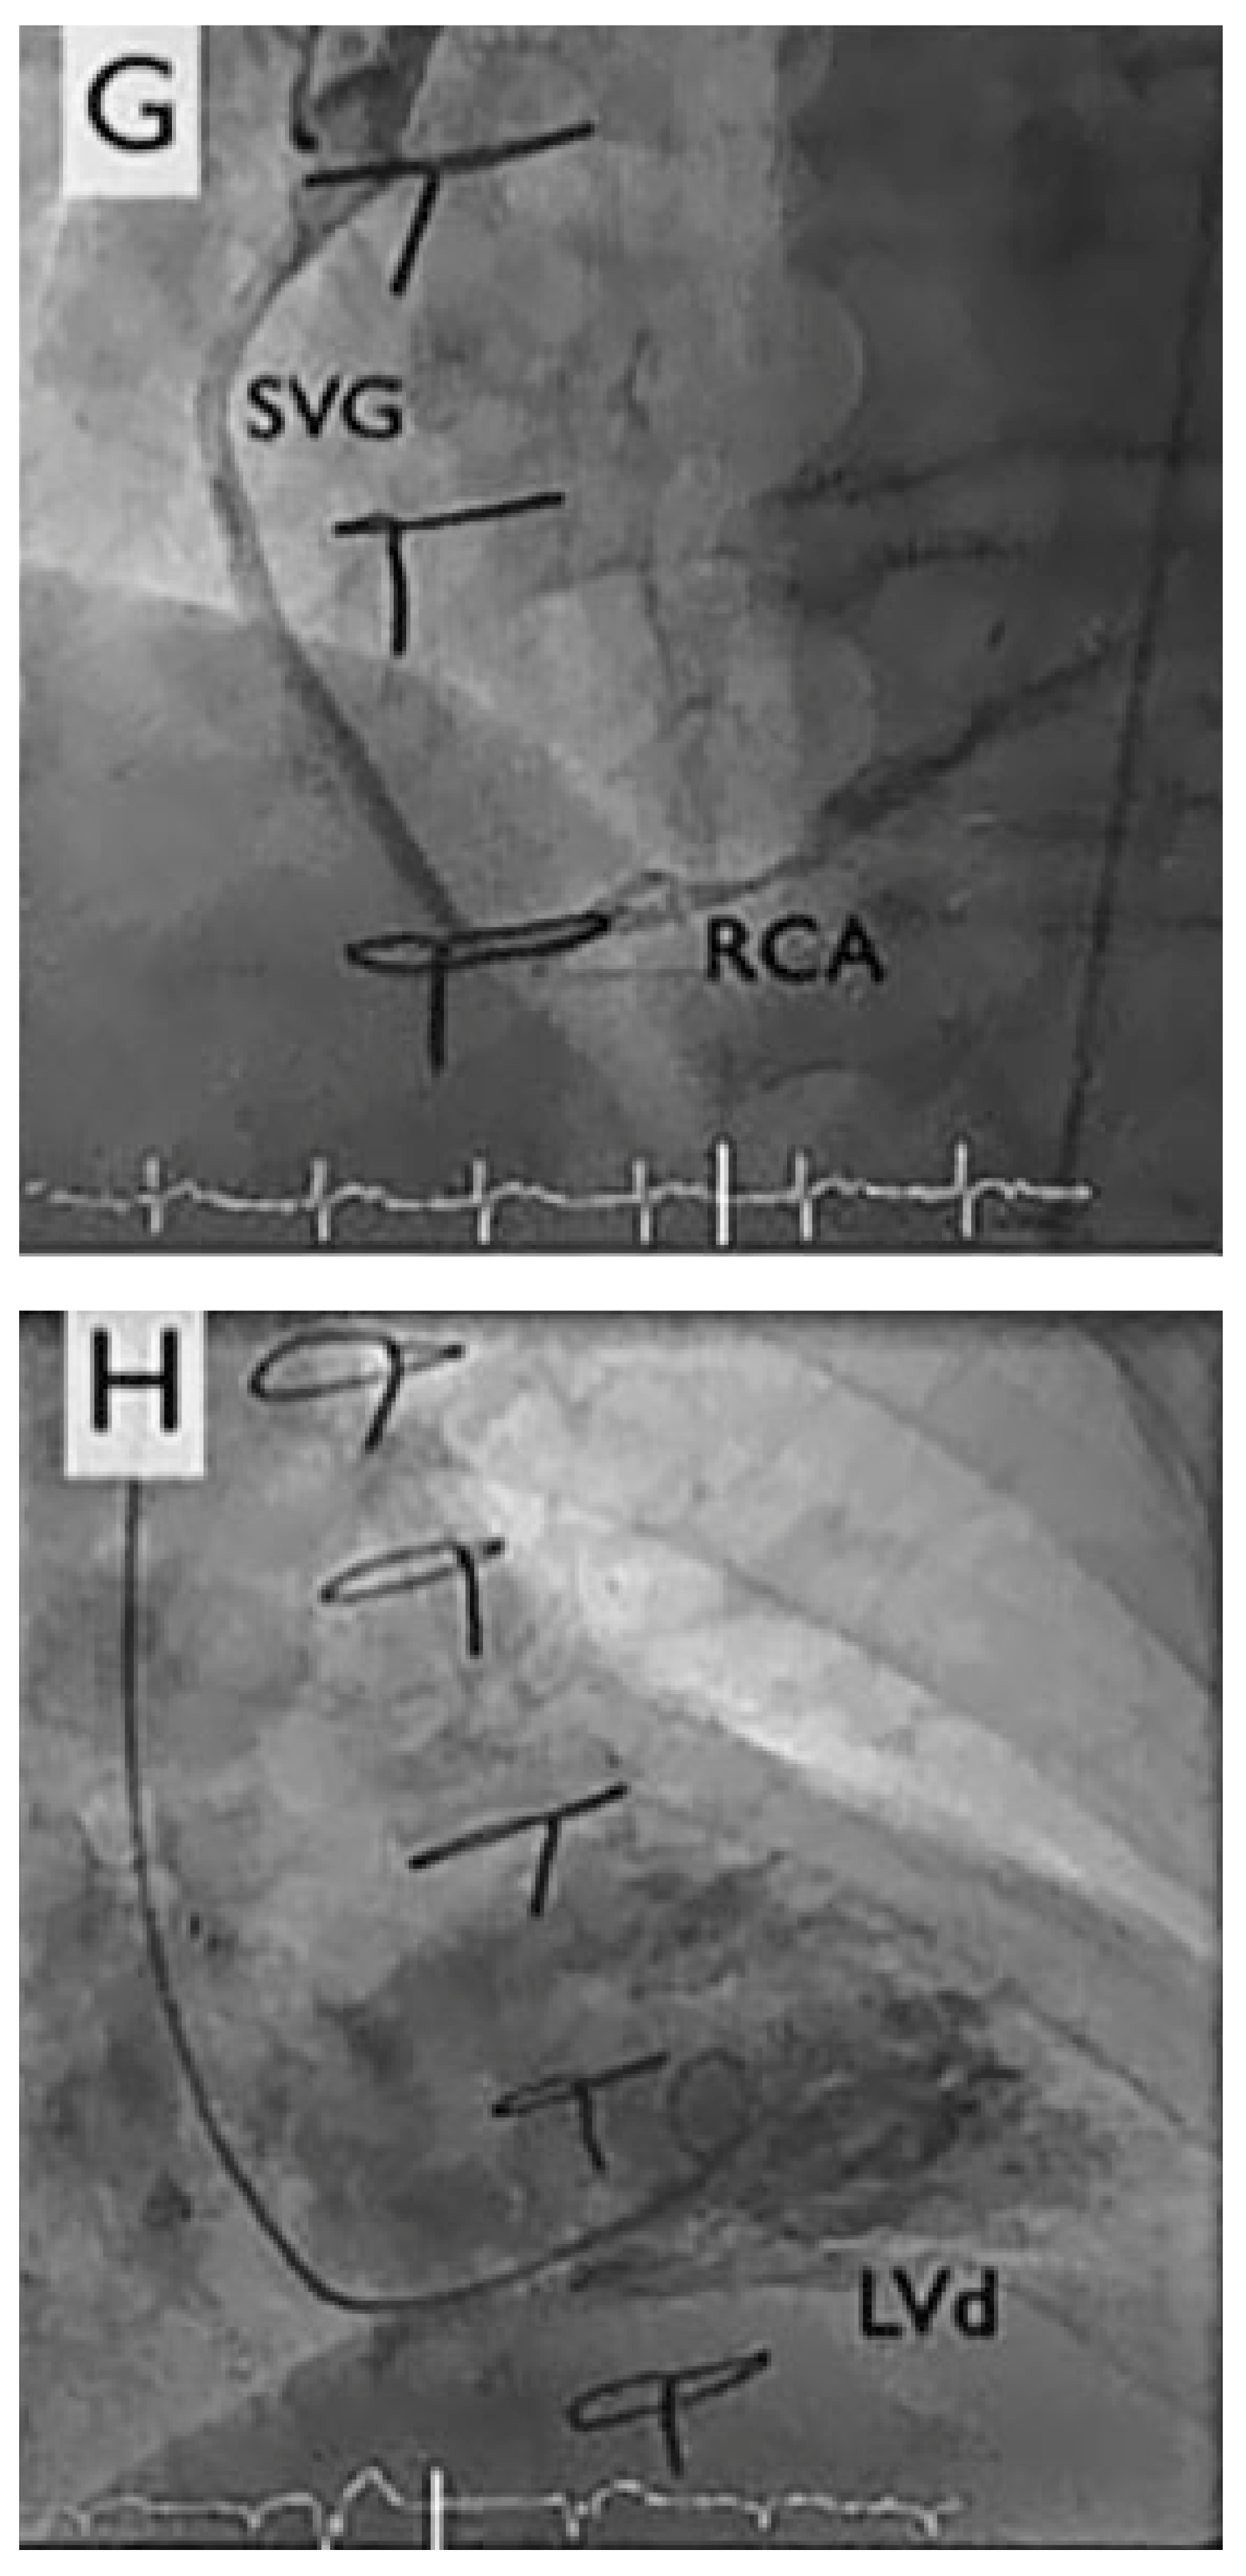

A 67-year-old diabetic patient with three-vessel coronary artery disease (Figure 1) and prior coronary artery bypass graft surgery (left internal mammary artery to left anterior descending artery, vein to marginal branch, vein to right coronary artery) suffered from refractory angina. Coronary angiography demonstrated good results after surgical revascularisation, but also a diffuse infiltration of the left coronary tree. Left ventricular systolic function was normal. The patient presented refractory angina despite optimal antianginal therapy comprising beta-blockers, nitrates, ranolazine (Ranexa®) and molsidomine (Corvaton®). The patient was severely disabled, being unable to walk 200 metres without nitrates, and waking up every 2 hours because of angina and paroxysmal dyspnoea. The treadmill test showed ischaemia.

Figure 1.

Coronary angiogram. LAD: left anterior descending artery, LCx: left circumflex artery, LIMA: left internal mammary artery, MA: marginal artery, RCA: right coronary artery, ous vein graft; LVS: left ventricular tele-systolic volume; LVD: left ventricular tele-diastolic volume.